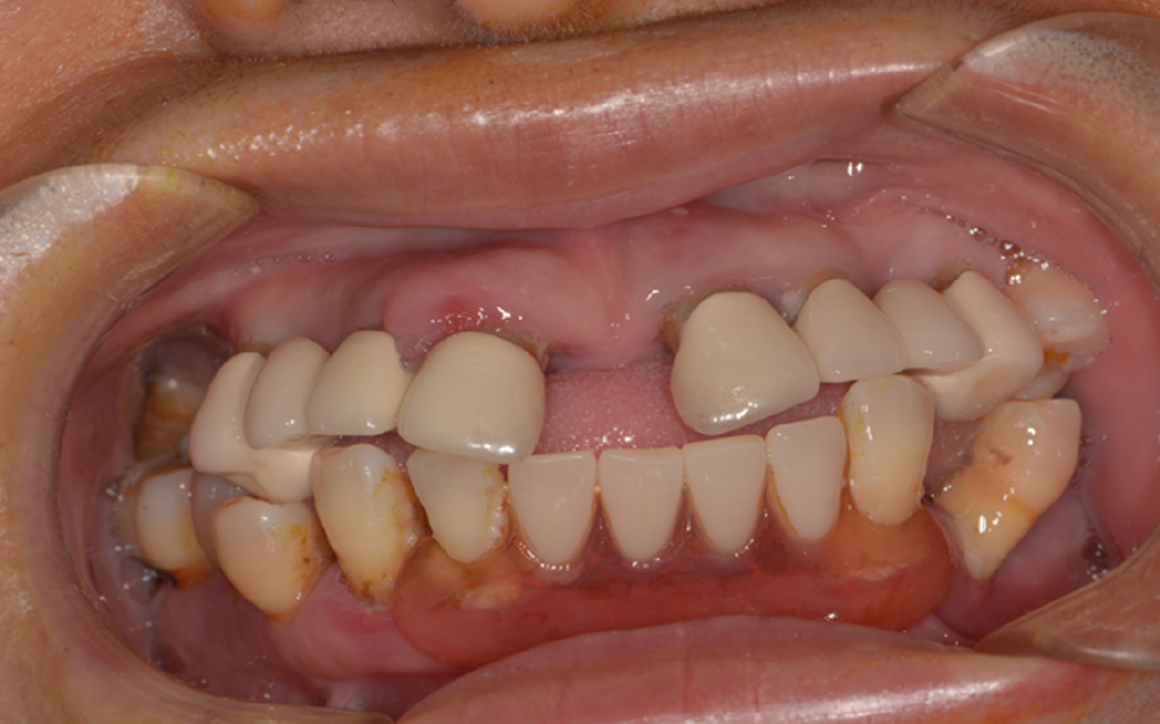

Реабилитация на диоксиде циркония

Проблема: Частичное отсутствие зубов, эстетика , страх стоматологов